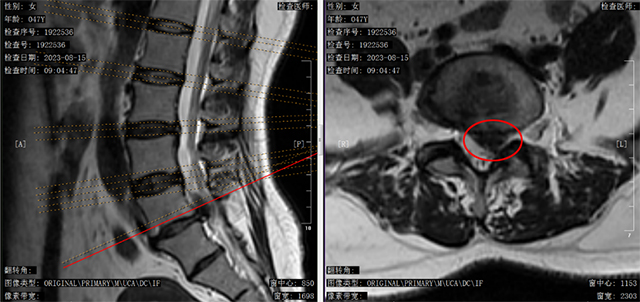

腰椎核磁共振可见:腰5-骶1椎间盘一块巨大的髓核脱出(即红圈内黑色物体)进入椎管并向头端游离,压迫了腰5左侧神经根

半小时后核磁结果证实常帅的判断:权女士腰5-骶1椎间盘一块巨大的髓核脱出进入椎管并向头端游离,压迫了腰5左侧神经根。